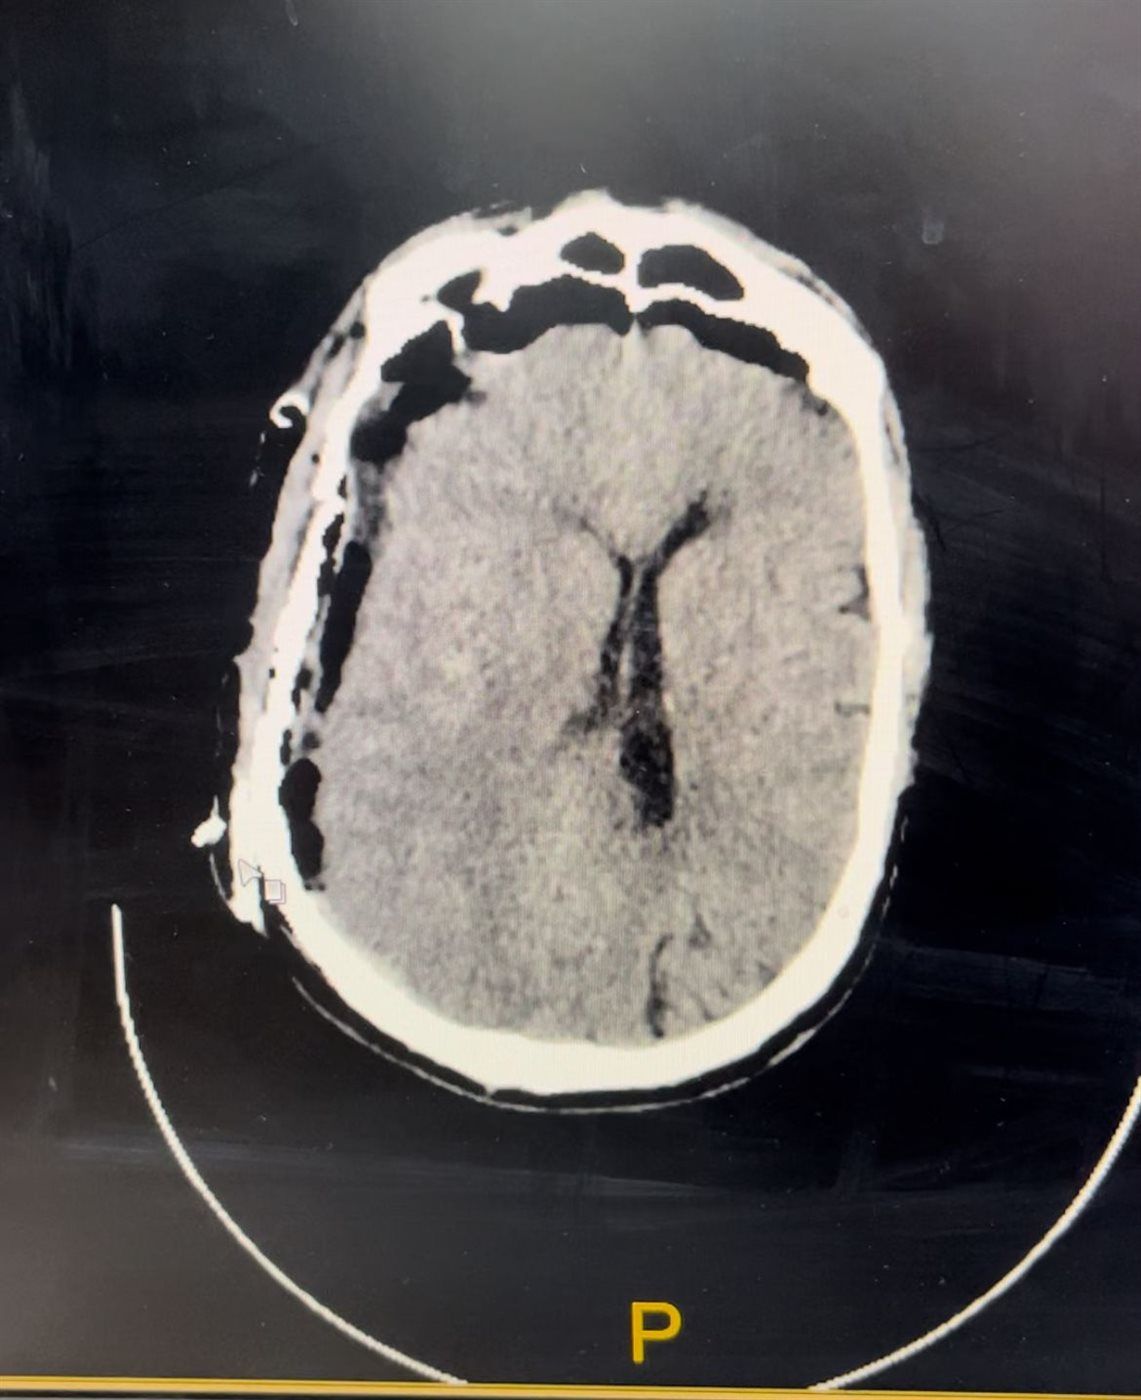

وأوضح أن الحالة كانت حرجة للغاية عند الوصول، حيث أظهرت الفحوصات وجود نزيف حاد أسفل الأم الجافية، ما استدعى التدخل الجراحي الفوري دون تأخير.

وأشار إلى أنه تم إجراء جراحة دقيقة لتفريغ النزيف والتحكم في الشريان النازف، مع متابعة الحالة بشكل مكثف داخل العمليات، مؤكدًا أن سرعة اتخاذ القرار والتدخل في الوقت المناسب كان لهما الدور الأكبر في إنقاذ حياة المريض وتحسن حالته بشكل كامل.